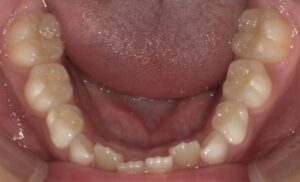

下顎ですが前歯に重なりが見られますが軽度で、

また奥歯と奥歯の幅は狭くありません。